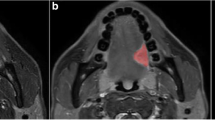

Discriminating metastatic from benign cervical lymph nodes (LNs) in oral squamous cell carcinoma (OSCC) patients using pretreatment computed tomography (CT) has been controversial. This study aimed to investigate whether CT-based texture analysis with machine learning can accurately identify cervical lymph node metastasis in OSCC patients.

Twenty-three patients (with 201 cervical LNs [150 benign, 51 metastatic] at levels I–V) who underwent preoperative contrast-enhanced CT and subsequent cervical neck dissection were enrolled. Histopathologically proven LNs were randomly divided into the training cohort (70%; n = 141, at levels I–V) and validation cohort (30%; n = 60, at level I/II). Twenty-five texture features and the nodal size of targeted LNs were analyzed on the CT scans. The nodal-based sensitivities, specificities, diagnostic accuracy rates, and the area under the curves (AUCs) of the receiver operating characteristic curves of combined features using a support vector machine (SVM) at levels I/II, I, and II were evaluated and compared with two radiologists and a dentist (readers).

In the validation cohort, the AUCs (0.820 at level I/II, 0.820 at level I, and 0.930 at level II, respectively) of the radiomics approach were superior to three readers (0.798–0.816, 0.773–0.798, and 0.825–0.865, respectively). The best models were more specific at levels I/II and I and accurate at each level than each of the readers (p < .05).

Machine learning–based analysis with contrast-enhanced CT can be used to noninvasively differentiate between benign and metastatic cervical LNs in OSCC patients.